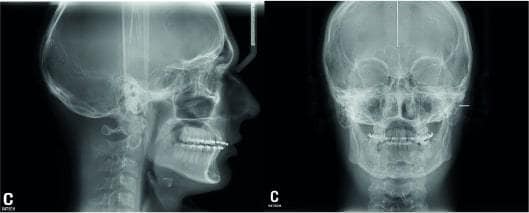

Типи зображень TRG розрізняють телерентгенограми у фронтальній і бічній проекції:

Телерентгенограма дозволяє отримати зображення, що відповідає розмірам і формі черепа.

Для лікаря-ортодонта знімок ТРГ в бічній проекції є обов'язковим для діагностики та планування лікування. Після цього проводяться математичні розрахунки.

Це дозволяє лікарю-ортодонту поставити правильний діагноз і визначити умови ортодонтичного лікування: тип росту, площину з’єднання зубів (площина оклюзії), нахил зубів і оптимальне розташування і просторове положення нижньої щелепи по відношенню до верхньої.